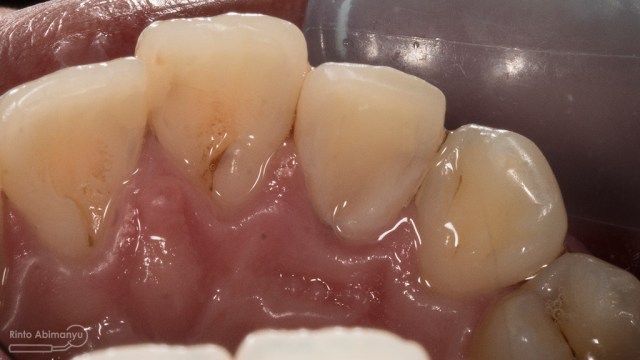

ini hasil preparasi gigi-giginya…

Hasil preparasi tampak depan

Hasil preparasi tampak oklusal